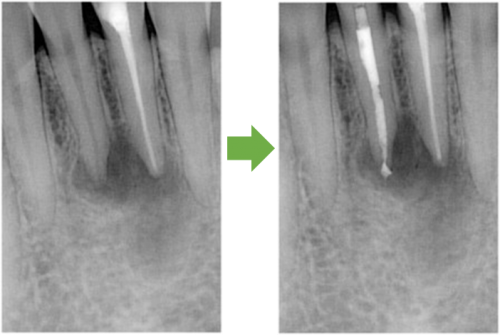

歯髄壊死 左上の前歯 川口の歯科 歯医者 さかえ歯科クリニック

2014年12月16日

術 前 術 後